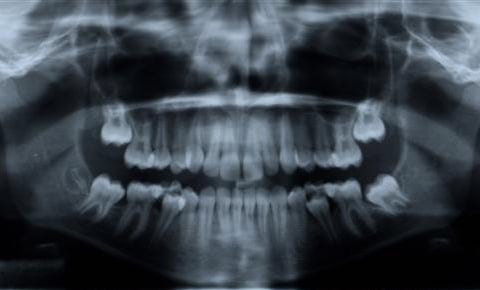

Panoramic X-Rays

Panoramic x-rays offer patients a complete detailed image of the entire mouth including the teeth, upper and lower jaws, sinuses and TMJ.

It provides a complete picture on how everything looks and relates to each other.